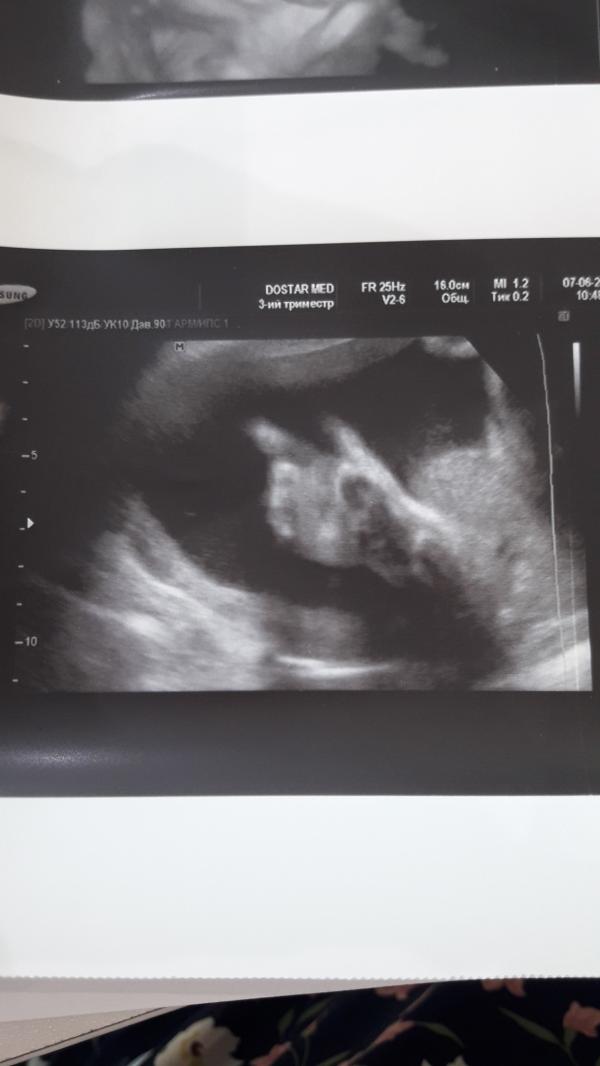

Моя малышка ❤❤❤😊😊😊

07.06.2019